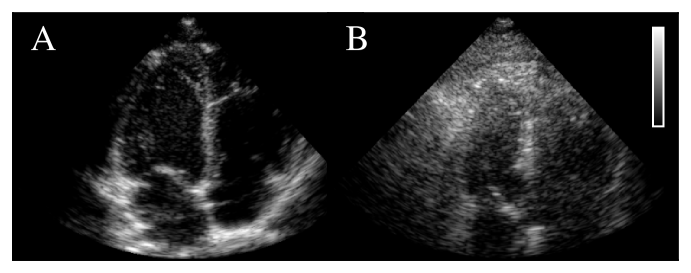

Refer to caption

Figure 1: Echocardiograms of easier (A) and difficult-to-image patients (B).